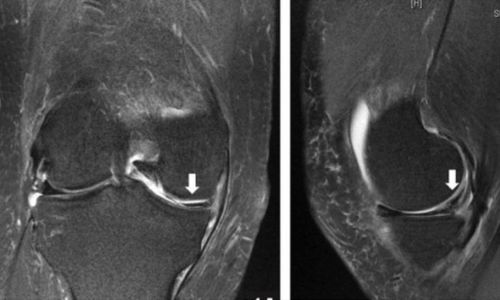

Εμφανίζεται συχνά σε νέους αθλητές στα πλαίσια αθλητικής κάκωσης ενώ παράλληλα μπορεί να εμφανιστεί και σε άτομα μεγαλύτερης ηλικίας με εκφυλιστική αιτιολογία (ηλικιακή φθορά).

Η διάγνωση γίνεται κλινικά μετά από τις κλινικές δοκιμασίες του ορθοπεδικού (π.χ. test Mcmurray) και η τελική επιβεβαίωση γίνεται μετά από απεικονιστικό έλεγχο με μαγνητική τομογραφία γόνατος.

Η ρήξη μπορεί να αφορά είτε τον έσω μηνίσκο (συχνότερα σε άτομα μεγαλύτερης ηλικίας) είτε τον έξω μηνίσκο (συνήθως η ρήξη αυτή συνυπάρχει με ρήξη πρόσθιου χιαστού συνδέσμου).

Η θεραπεία είναι είτε χειρουργική (αρθοσκοπική συρραφή μηνίσκου ή αρθοσκοπική μηνισκεκτομή) είτε συντηρητική αντιμετώπιση. Η απόφαση για το είδος της θεραπείας γίνεται πάντα μετά από συζήτηση και λεπτομερή ανάλυση του ορθοπεδικού ιατρού με τον ίδιο τον ασθενή λαμβάνοντας υπ' όψιν παράγοντες όπως η ηλικία του ασθενούς, το είδος της ρήξης, τα συμπτώματα που οδήγησαν τον ασθενή να ζητήσει βοήθεια καθώς και το επίπεδο αθλητικής δραστηριότητας του ασθενούς.